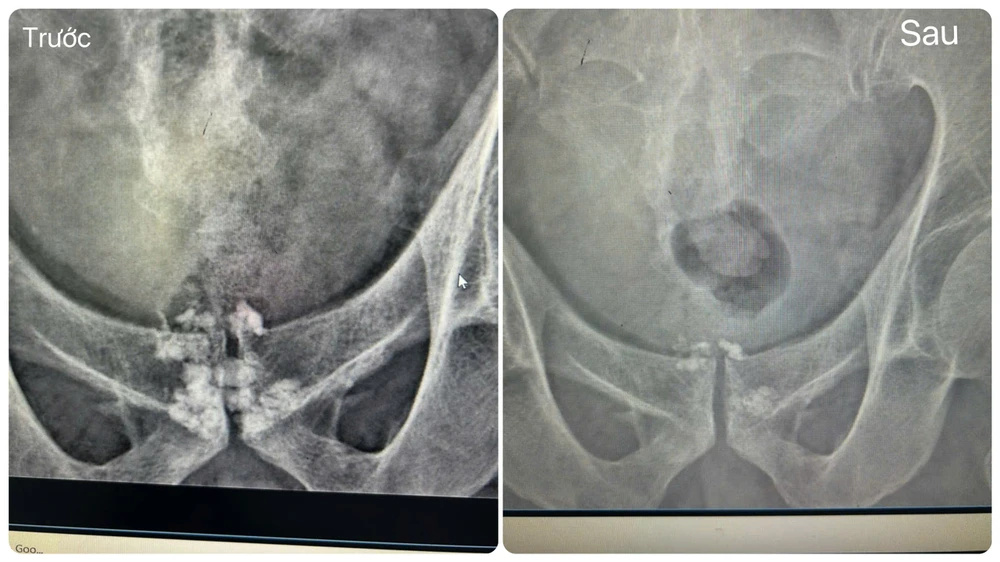

soi-tiet-nieu-12.jpg

Hình ảnh trước và sau khi cắt đốt tiền liệt và tán sỏi của ông Hồng. Ành: BVCC